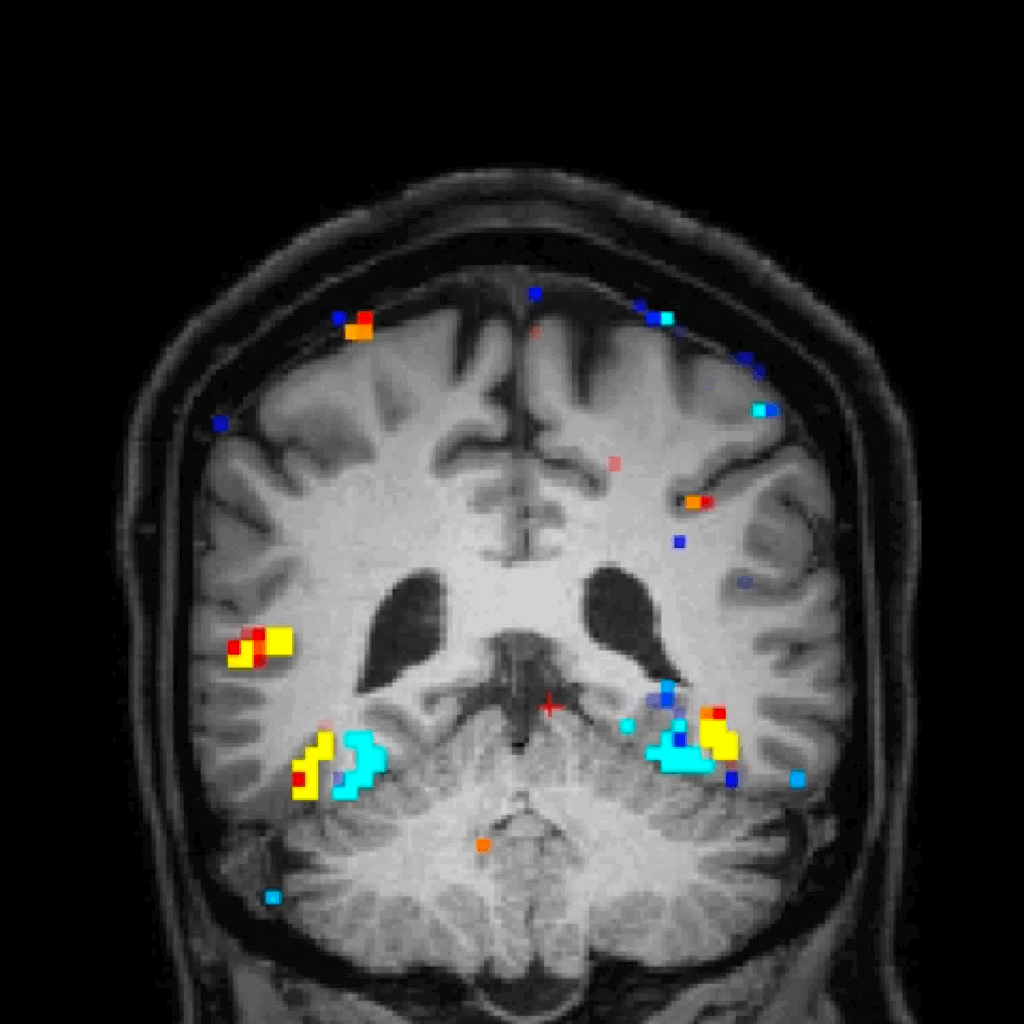

By combining advanced brain imaging with cutting-edge molecular analysis, researchers at the Allen Institute and the University of Washington (UW) School of Medicine are building a detailed map of the human brain that connects how it’s built to how it functions. This work, powered by study participants who generously volunteer to donate their brains after they die, is laying the foundation for improved treatments for conditions like Alzheimer’s, brain injury, depression and more.

With MRI brain scans from living participants combined with microscopic analysis of brain tissue after death, researchers are uncovering how specific brain structures and cell types relate to memory, language, emotion, and disease.

A non-invasive MRI scan to capture how your brain works while you watch and listen to videos, and an opportunity to donate your brain after death.

Understanding the brain is one of science’s greatest challenges and greatest opportunities. “By linking MRI scans with cellular-level data, this study gives us an unprecedented window into the living human brain,” said Ed Lein, Ph.D., Senior Investigator at the Allen Institute. “That connection is key to understanding – and eventually treating – brain disease.”